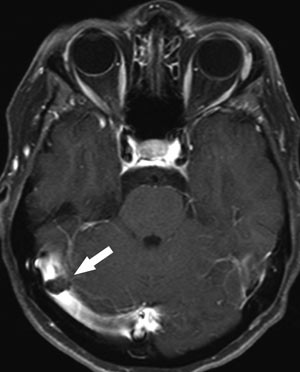

Et typisk bildediagnostisk tegn ved cerebral venetrombose er en fyllingsdefekt i venesinus (fig 1). Disse fyllingsdefektene er hypertette på CT. I sinus sagittalis superior vil fyllingsdefekten ofte ha en trekantet form. På MR vil signalet i tromben variere med alderen (fig 2). Trombene kan også strekke seg retrograd fra venesinus og inn i de kortikale venene. Sekundære forandringer til sinusvenetrombose er hjerneødem og venøse infarkter, typisk beliggende subkortikalt og kortikalt (fig 3). I motsetning til arterielle infarkter vil de venøse ikke følge forsyningsområdene for de store cerebrale arteriene, en annen forskjell er større ødem ved venøse infarkter (18). Venøse infarkter vil ofte være hemoragiske, og på såkalte hemosekvensbilder vil man se blodproduktene som områder med lavt signal.

Ved bildediagnostikk av cerebral venetrombose er det viktig å være oppmerksom på noen fallgruber. Det er en betydelig grad av anatomiske variasjoner i de durale venesinuser, dette gjelder særlig i sinus transversus. Hos vel to tredeler av alle mennesker er høyre sinus transversus større enn venstre. Sinus transversus er hypoplastisk eller manglende på den ene siden hos nær en tredel, vanligvis på venstre side. En manglende fremstilling av sinus transversus må derfor ikke uten videre tolkes som en okklusjon fremkalt av trombe (fig 4). Pacchioni-granulasjoner i venesinuser er en normalvariant (19). Disse granulasjonene kan bli opptil et par centimeter og delvis okkludere venesinus (fig 4). De kan skilles fra tromber ved at de har en typisk lokalisasjon ved innmunningen av Labbes vene i sinus transversus og ved at signalmønsteret er annerledes.